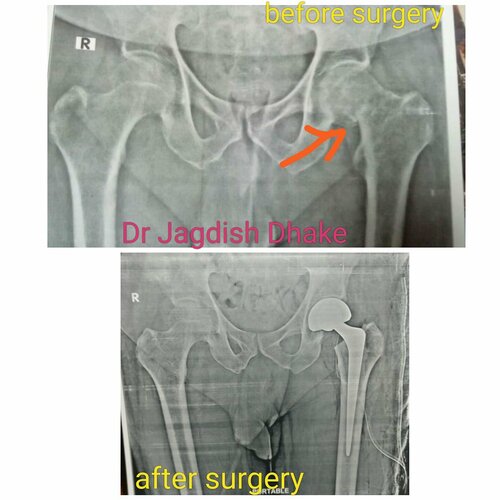

Intertrochanteric Fracture Femur | Dr. Jagdish Dhake

78 year female patient had intertrochanteric fracture femur, operated by Dr. Jagdish Dhake - Orthopedic Surgeon in Bibvewadi with Proximal femoral nai...